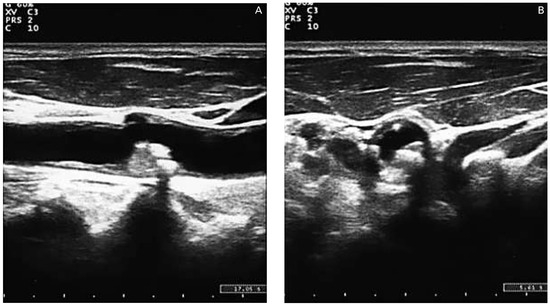

Carotid Ultrasonography in the Assessment of Cardiovascular Risk

by Aldo Pende, Nathan Artom, Giovanni Pistocchi, Livia Pisciotta and Franco Dallegri

Cardiovasc. Med. 2015, 18(2), 61; https://doi.org/10.4414/cvm.2015.00309 - 18 Feb 2015

Carotid ultrasound is one of the most accessible examinations in daily clinical practice for the evaluation of the arterial status. However, the clinical implications of the presence, the extension and the morphology of carotid damage are not entirely clear. Aim of this narrative [...] Read more.

Carotid ultrasound is one of the most accessible examinations in daily clinical practice for the evaluation of the arterial status. However, the clinical implications of the presence, the extension and the morphology of carotid damage are not entirely clear. Aim of this narrative review is to discuss the role of carotid ultrasound in the assessment of cardiovascular risk through the examination of the updated evidence in the literature. We describe the technical aspects of the procedure and the possible correlations between the imaging results and the assessment of the cardiovascular risk. Some insights about new, more sophisticated techniques for carotid evaluation, such as carotid three-dimensional and contrast-enhanced ultrasound, are also presented. Full article

Show Figures

Figure 1